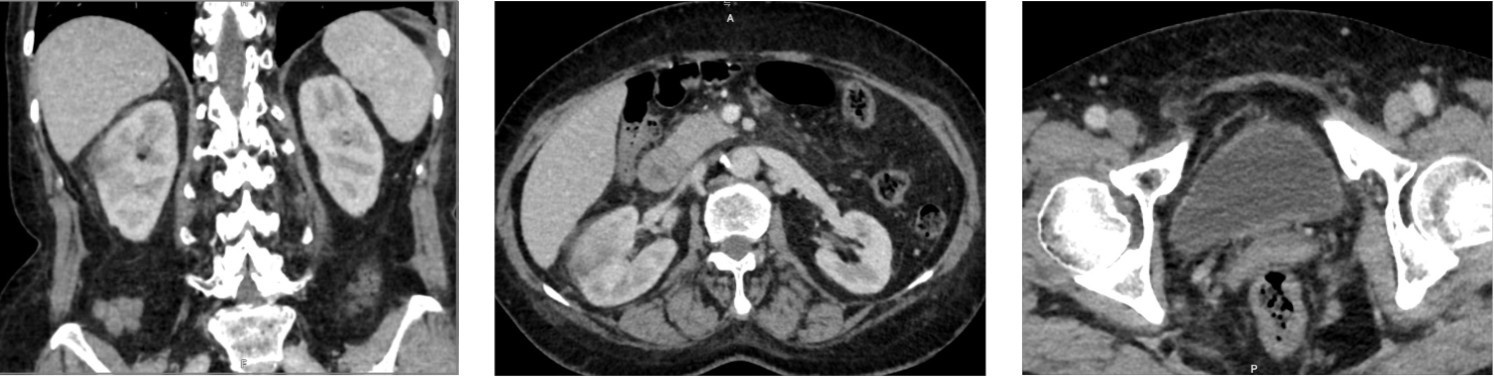

| Hình ảnh theo dõi viêm thận bể thận bên phải trên MRI. |

Tại bệnh viện, người bệnh được chỉ định thực hiện các xét nghiệm vi sinh và chẩn đoán hình ảnh chuyên sâu. Kết quả nuôi cấy máu và nước tiểu đều dương tính với vi khuẩn Klebsiella pneumoniae, một trong những tác nhân gây nhiễm trùng nguy hiểm. Siêu âm ổ bụng phát hiện nốt vôi hóa gan phải và nang thận phải.

Trên phim chụp CT có tiêm thuốc cản quang, các bác sỹ ghi nhận hình ảnh gợi ý viêm thận bể thận phải kèm theo nang thận phải. Từ các kết quả trên, bệnh nhân được chẩn đoán nhiễm khuẩn huyết có nguồn gốc từ đường tiết niệu.

Chẩn đoán hình ảnh như siêu âm, CT hoặc MRI cũng được chỉ định trong nhiều trường hợp, đặc biệt khi biểu hiện lâm sàng không điển hình, bệnh nhân không đáp ứng điều trị sau 48 đến 72 giờ, có yếu tố nguy cơ cao như đái tháo đường, sỏi tiết niệu, suy giảm miễn dịch hoặc cần tìm ổ nhiễm và tầm soát biến chứng như áp xe, hoại tử, tắc nghẽn đường tiết niệu.